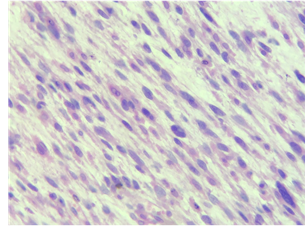

El estudio anatomopatológico informa leiomiosarcoma de alto grado, de 25.5 x 22 x 9 cm, grado histológico 2 (moderadamente diferenciado) T4 Nx Mx, con fibras alargadas, haces extensos y entrecruzados de células fusiformes con núcleos alargados, necrosis 40%, tasa mitótica < 5 en 10 hpf, (Fig. 5). Por su parte, el estudio citoquímico arroja leucocitos de 552mm3, polimorfonucleares de 28%, mononucleares de 72%, glucosa 138mg/dL, deshidrogenasa láctica de 1,823 U/L. No se cuenta con resultados del estudio citológico.

Fig. 5 Leiomiosarcoma moderadamente diferenciado con fibras alargadas, hacer extensos y núcleos alargados (HE x 400).

Macroscópicamente los leiomiosarcomas se perciben como masas de color blanco- carnosas, con focos de hemorragia y necrosis, indistinguibles de otros sarcomas. Mientras que microscópicamente se componen de fascículos largos, con citoplasma abundante, el núcleo suele estar centralmente localizado con extremos romos similar a la forma de un cigarro.3,11.